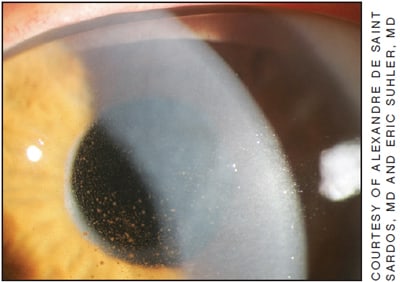

Figure 1. IFIS, characterized by iris billowing and prolapse, can occur in patients taking Flomax or a similar drug.